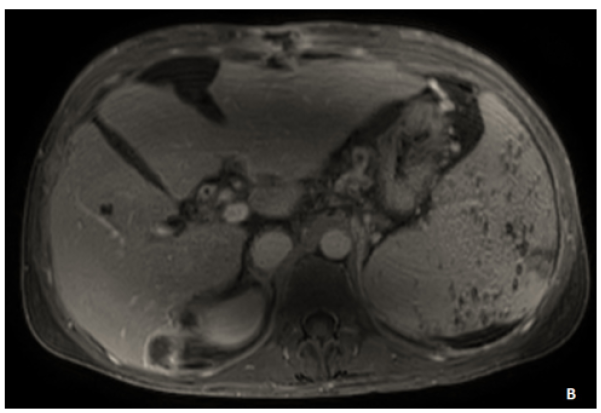

From Gamma Gandy Bodies to Geographic Enhancement: An Imaging Approach to Diagnosing Congestive Splenomegaly

Yassine Zerhari, Asaad El Bakkari, Mohammed Ennmer, Hatim Essaber, Soukaina Allioui, Hounayda Jerguigue, Youssef Omor and Rachida Latib. 6(5): 58-60.